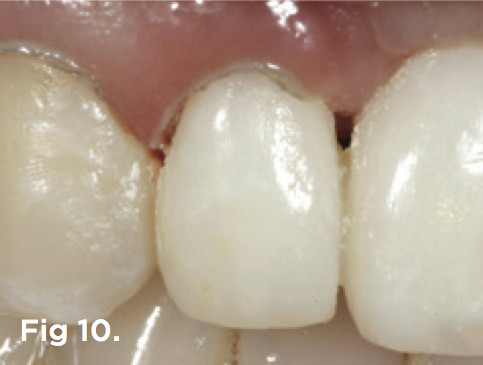

Fig 10. After a few weeks of healing of the soft tissues after non-surgical tissue sculpting, a gingivectomy was done to re-shape the gingival zenith and levels of teeth Nos. 6 through 8.

Figure 10

After 6 months of healing of the implant, stage 2 uncovering was performed and the mucosal tissues were allowed to mature for another 2 to 3 weeks. A temporary screw-retained implant cylinder was joined to the implant and acrylic crown (Figure 8). The subgingival shape of the temporary was modified with additional acrylic and the technique of non-surgical tissue sculpting, which was developed to provide the proper emergence profile to the mucosal tissues.27 It is important that the temporary blanching (ischemia) of the mucosal tissues dissipate after 10 minutes (Figure 9). After 3 weeks, soft-tissue scalloping through gingivectomy was done to recreate the proper shape (ie, gingival zenith)28 and proportion for the mucosal tissues (Figure 10). Fiberotomy on the distal aspect of tooth No. 7 was not performed during treatment; therefore, this papilla was slightly more incisal (longer) than the adjacent papillae (Figure 11). A final impression was made of crown No. 7 and implant No. 8 at the implant level to enable a working cast to be made in the laboratory. An all-ceramic custom abutment was made for implant No. 8, and splinted full-coverage units were made for crowns No. 7 and No. 829 (Figure 12). The custom abutment was seated intraorally and torqued according to the manufacturer’s recommendation. The crowns were luted with provisional cement and maintained at 4-month recall intervals (Figure 13). Note the health of the periodontal tissues and its integration with the adjacent teeth and surrounding gingiva, taking a complex esthetic and functional problem for a patient with a high smile line and providing a predictable restorative and esthetic outcome (Figure 14).